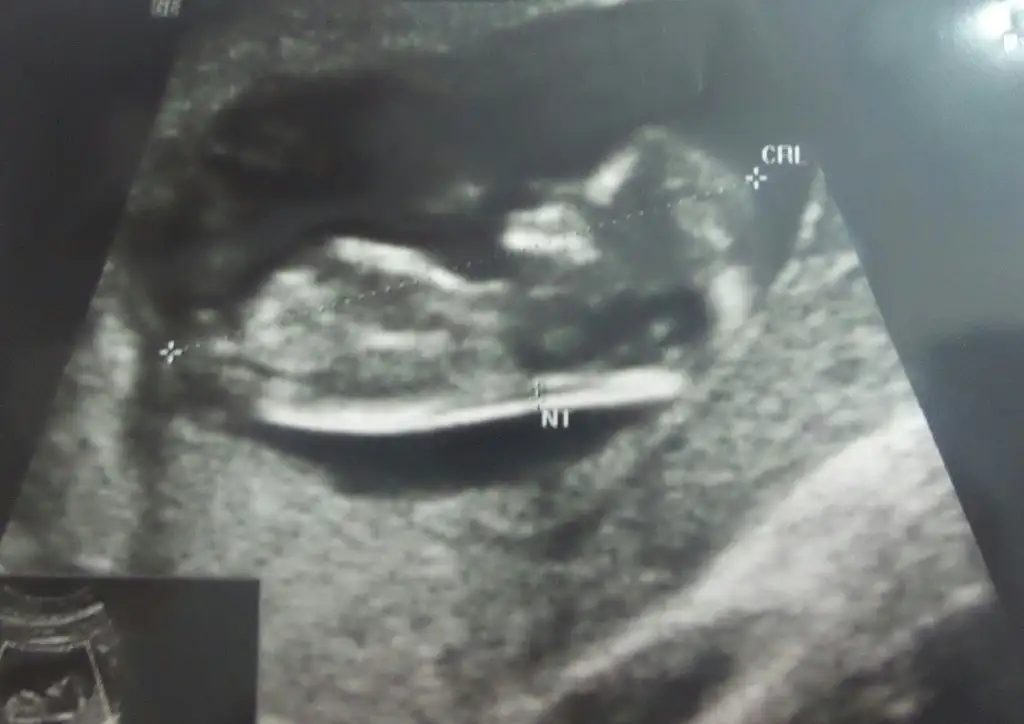

selam arkadaslar dun de sormustum ama bilen yok mu acaba ultrason kagidinda fta diye yazan ne bilen var mi ??

Bende yazmıyor öyle bişi, 4 boyutlu da mı yazıyor?selam arkadaslar dun de sormustum ama bilen yok mu acaba ultrason kagidinda fta diye yazan ne bilen var mi ??

Hiç bilmiyorum canım,selam arkadaslar dun de sormustum ama bilen yok mu acaba ultrason kagidinda fta diye yazan ne bilen var mi ??

canim cok ovuolar evrimi ama herkede ayni sonuci vermio tabi. sanki erkek pipis gordum gbi ama cok erken 11.hafta bende rentipta nazmiye hanima gidiyorum oda 12.haftada yapmadi 15 .haftada kesinlesio dediCinsiyetten anlayan varmı bi baksanıza lütfenn..

canım ya dr lar ancak anlayabilir gibi pek bişe belli değil.